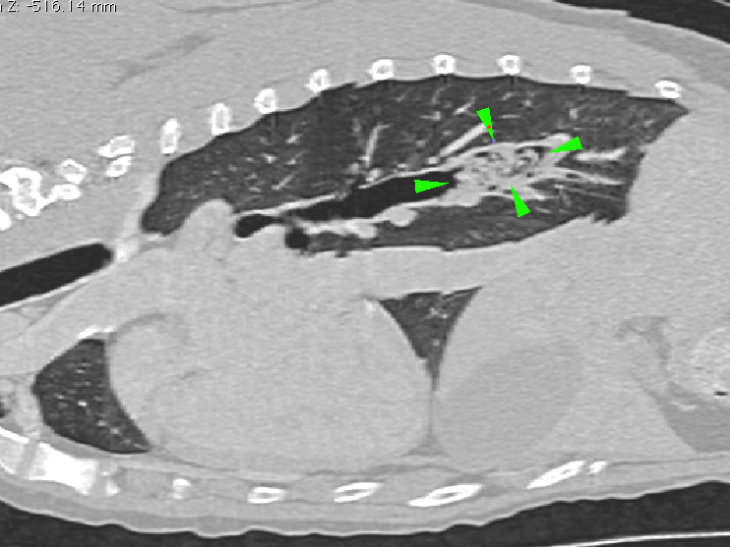

CT sagittal view of the chest

CT sagittal view of the chest. The main right caudal bronchus is partially occluded by a foreign

body with soft tissue density (green arrowheads).

There is a mild amount of gas bubbles trapped by the foreign body.